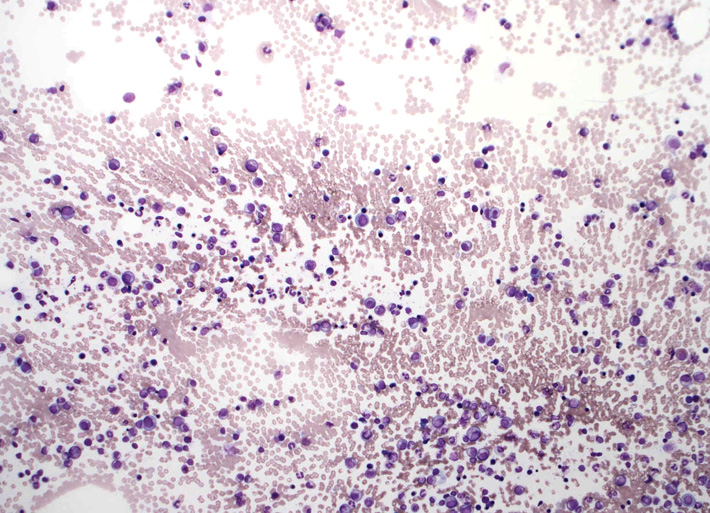

骨髄スメア標本です。ねっとりした血清成分がよくわかります。「hyperviscosity」の状態= 過粘稠(ねんちゅう-と読むらしい)症状; hyperviscosityの正しい訳は過粘度のほうがよいと思う.

赤血球が索状に連なる連銭形成rouleauxが明瞭です。

bone marrow clot section(May-Giemsa染色)標本

metachromatic basophilic granulesをもつmast cellが多数出現する

plasmacytoid lymphocyte